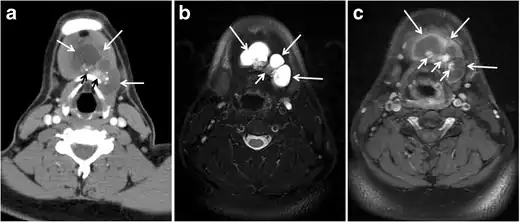

Fig. 6. A 61-year-old female patient with locally aggressive PTC. an Enhanced axial CT scan of the neck demonstrates a heterogeneous infiltrative thyroid mass. This mass diffusely involves the entire gland and circumferentially encases the trachea with involvement of bilateral tracheoesophageal grooves (white arrows). b, c Additional axial cranial images show right cricoid cartilage destruction (black arrows in b), right thyroid cartilage destruction (black arrow in c), right vocal cord paralysis (white arrows in b), and bilateral cervical lymphadenopathy (arrowheads).[1]

The radiologist must evaluate the central structures draping the thyroid gland including the trachea, oesophagus, larynx, and pharynx, as well as the recurrent laryngeal nerve. Invasion is suspected if the thyroid mass abuts the airway or oesophagus for more than 180 degrees. Luminal deformity, mucosal thickening and mucosal focal irregularity are more specific indicators of invasion. Obliteration of the fat planes of the tracheoesophageal groove in three axial images and signs of vocal cord paralysis are indicative of recurrent laryngeal nerve invasion. Invasion of these central structures meets the criteria for T4a disease (Figs. 5 and and6)6).[1]

Arterial invasion constitutes T4b disease, which may preclude curative surgery. More than 180 degrees of arterial encasement is suggestive of invasion, however, arterial deformity or narrowing is much more suspicious for invasion. The carotid artery is the most commonly involved artery; however, the mediastinal vessels should also be examined. Encasement of the carotid artery or mediastinal vessels for more than 270 degrees is unlikely to be resectable. On the other hand, occlusion or effacement of the internal jugular vein can occur without invasion and does not influence surgical resectability or staging. Asymmetry of the strap muscle and the tumour abutting its external surface are signs of an invasion. However, invasion of the pre-vertebral musculature is more challenging, as a large lesion can compress the muscle without invasion (Figs. 5 and and6)6).[1]